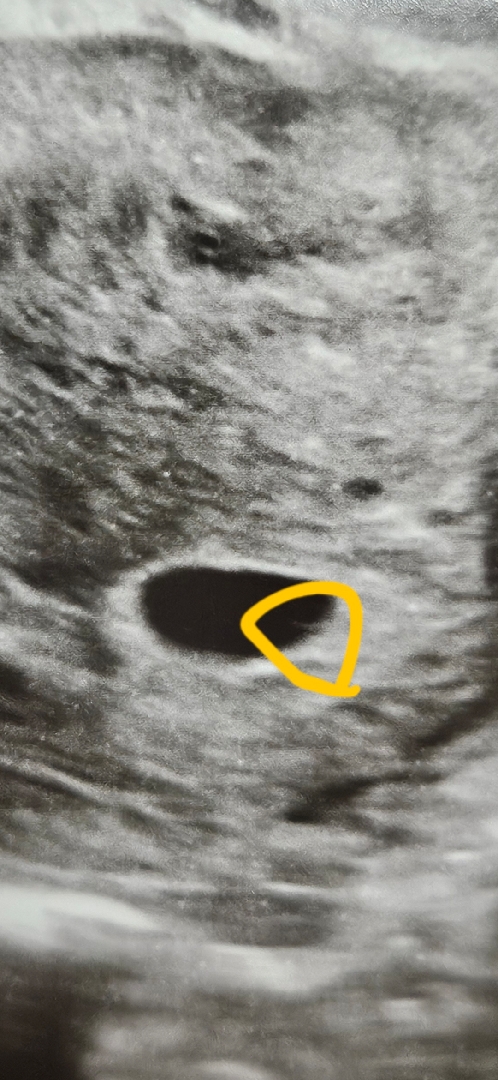

아기집에 이거 난황일까요?

5주3일차 사진입니다. 난황처럼 보이시나요??

저두 선생님이 난황 생기는거라고 하시던데요

저도 저렇게 거의 안보여서 있는거냐고 물어보니 맞다하시더라구요

저두 이랬는데 일주일 뒤인 오늘 난황이 생겨있더라구요